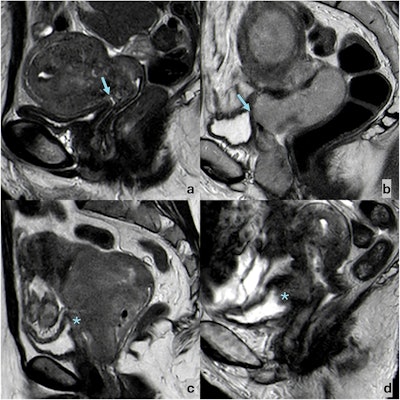

Sagittal T2-weighted FSE images showing the possible appearances of bladder wall–cervical cancer relation. (a) A fatty cleavage plane (arrow) may be observed between CC and the bladder, which shows a thin T2-hypointense wall. (b) The fatty cleavage plane between CC and the bladder is obliterated (arrow), but the bladder wall appears thin and T2-hypointense. (c) The fatty cleavage plane between CC and the bladder is obliterated, and the bladder wall appears thickened, with intermediate signal intensity (star). (d) The fatty cleavage plane between CC and the bladder is obliterated, the bladder wall appears thickened, with intermediate signal intensity, and neoplastic tissue protrudes in the bladder lumen (*).Bonatti et al; European Radiology